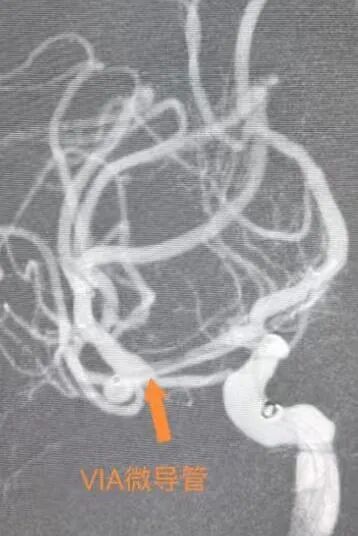

面對兩難境地,姜紅升主任團隊協(xié)同西院區(qū)麻醉科深入研討,對患者自然風險、手術(shù)策略、并發(fā)癥預防和處理預案、圍手術(shù)期用藥和預后康復等情況進行了充分的討論。經(jīng)過與患者家屬耐心細致地溝通,最終確定采用瘤內(nèi)擾流裝置(WEB?)植入術(shù)的治療方案。該裝置像一把量身定制的“傘”,被直接送入動脈瘤內(nèi)部,通過巧妙干擾內(nèi)部血流,促使瘤體自行閉塞,可有效密封動脈瘤頸而不影響載瘤動脈,且手術(shù)操作簡單,避免了超選分支血管的難度。術(shù)后患者亦無需長期服藥,一舉解決多個核心難點。

在充分的術(shù)前準備和多科室協(xié)作下,姜紅升主任團隊憑借精湛技術(shù),成功為患者植入了WEBTM裝置。手術(shù)過程順利,術(shù)后患者恢復良好,無任何不適,術(shù)后6天辦理出院。